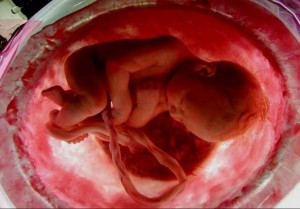

Довольно серьезным испытанием для будущей мамочки становятся анализы на выявление патологии. Обычно их проводят с 10 по 16 неделю, то есть в первом триместре. В некоторых случаях врачи вынуждены констатировать врожденные или генетические отклонения, из-за которых рекомендуется прерывание беременности. Какая самая опасная патология беременности на ранних сроках, как она может повлиять ни ребенка и есть ли шансы ее избежать?

При наличии этих факторов шансов на развитие генных мутаций у плода значительно больше. Выявление патологий на ранних сроках беременности позволяет обнаружить нежизнеспособные эмбрионы. В основном это приводит к замершей беременности или рождению детей с отклонениями.

Диагностика развития патологии плода

УЗИ плода

Если предыдущий анализ на патологию плода позволяет выявить генные отклонения, то УЗИ позволяет исключить врожденные патологии. Однако проводить его можно только при условии, что специалист опытный именно в вопросах пренатальной диагностики ВПР, а также с 20 недели после зачатия. Не рекомендуется экономить, обращаясь в более дешевые диагностические центры. Вполне вероятно, они использую устаревшее оборудование, с которым выявить патологию невозможно.